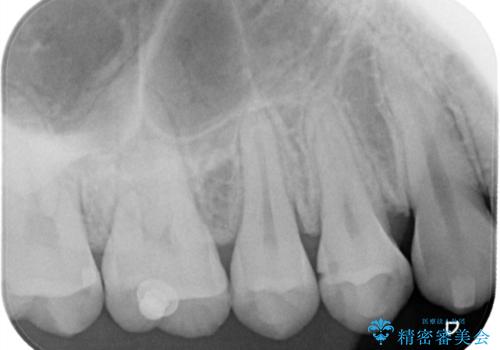

【セラミックインレー】歯と歯の間の虫歯治療

- 歯と歯の間に虫歯が見つかったため、拡大鏡を使用して丁寧に虫歯を除去し、セラミックインレーにて修復治療をおこないました。

セラミックインレーはレジン(プラスチック)と違い、形態の付与がしやすく、長期的な安定性が高い治療です。